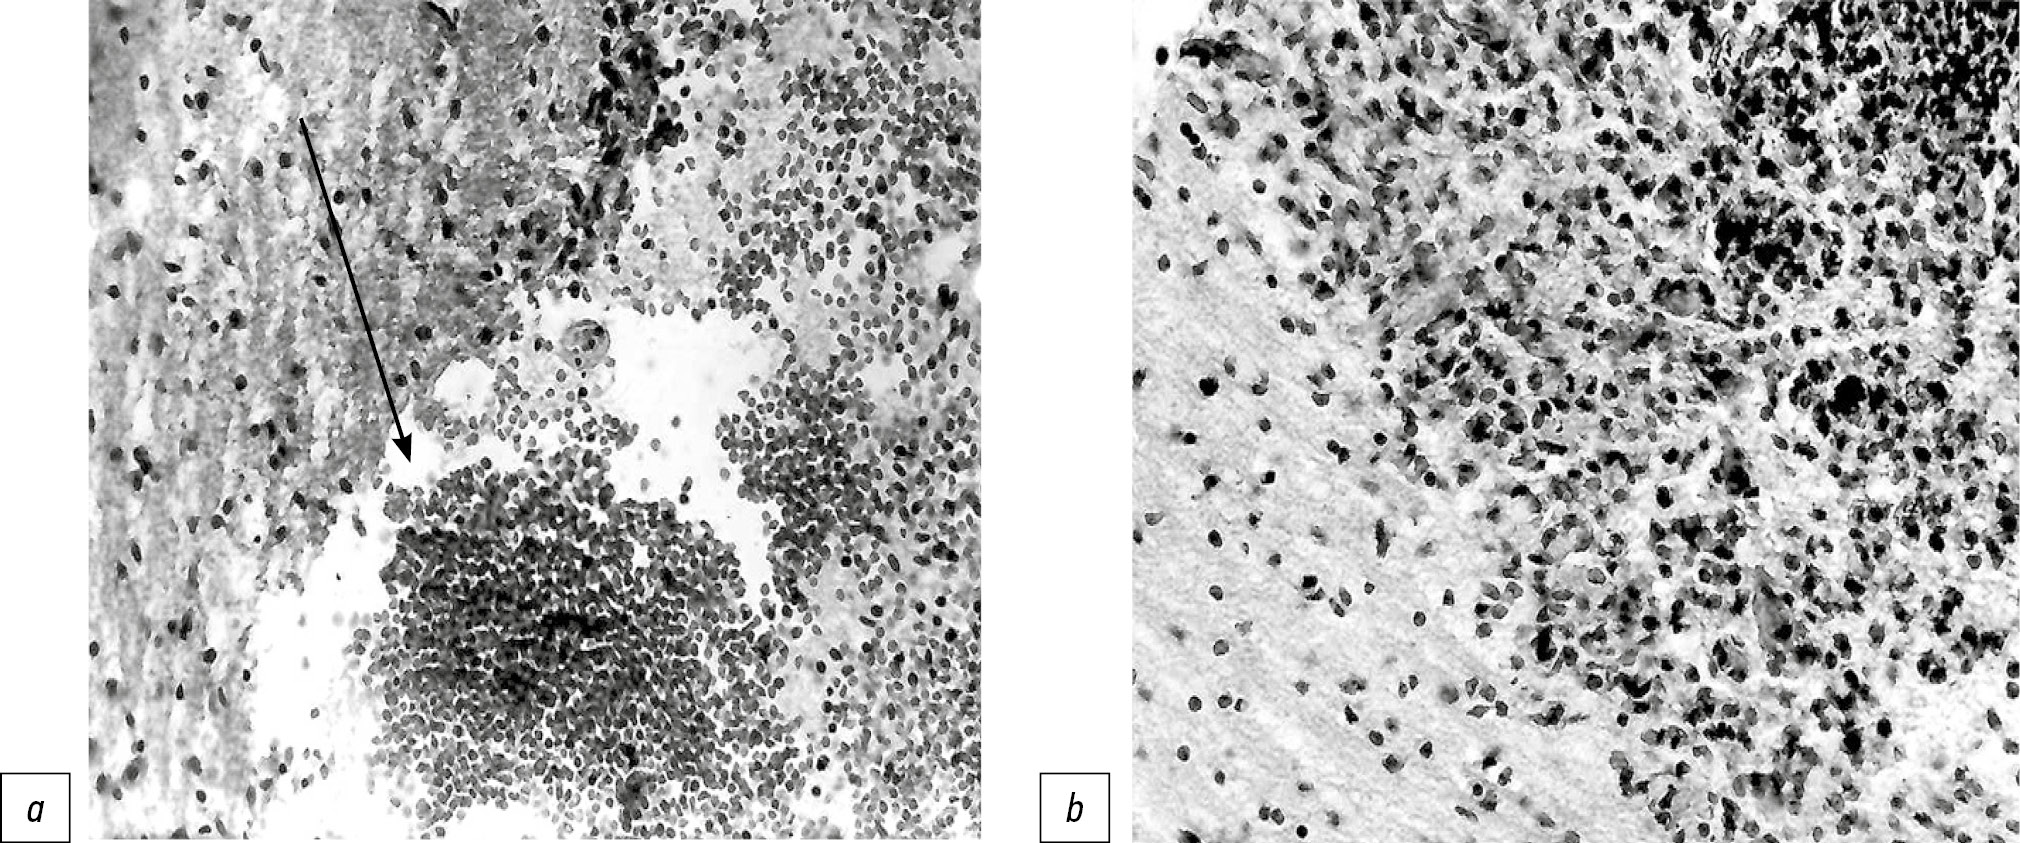

Очаг повреждения имел площадь 4091,7±381,8 мкм2. В первые сутки после операции он был представлен полостью, заполненной бесструктурными массами (рис. 3, a). На 2–3-е сутки после операции вокруг очага некроза скапливалось умеренное число глиальных клеток (преимущественно астроцитов), среди которых находились клетки макрофагального типа (вплоть до формирования зернистых шаров на 3–5-е сутки). На 5-е сутки после операции отмечалась пролиферация астроцитов (рис. 3, b). Через 7–9 сут на месте повреждения обнаруживалась небольшая полость, окружённая тонкой глиальной капсулой, а позднее в мозговой ткани выявлялся небольшой глиальный рубец.

Рис. 3. Головной мозг плода кролика, травмированное полушарие: a — зона повреждения (1-е сутки после операции); b — участок мозговой ткани вблизи от зоны повреждения, пролиферация астроцитов с примесью небольшого количества молодых соединительнотканных клеток (5-е сутки после операции). Окраска гематоксилином и эозином, ×400.

Fig. 3. The brain of a rabbit fetus, injured hemisphere: a — damage zone (on the 1st day after surgery); b — area of brain tissue close to the damaged area, proliferation of astrocytes with an admixture of a small amount of young connective tissue cells (on the 5th day after the operation). Stained with hematoxylin and eosin, ×400.